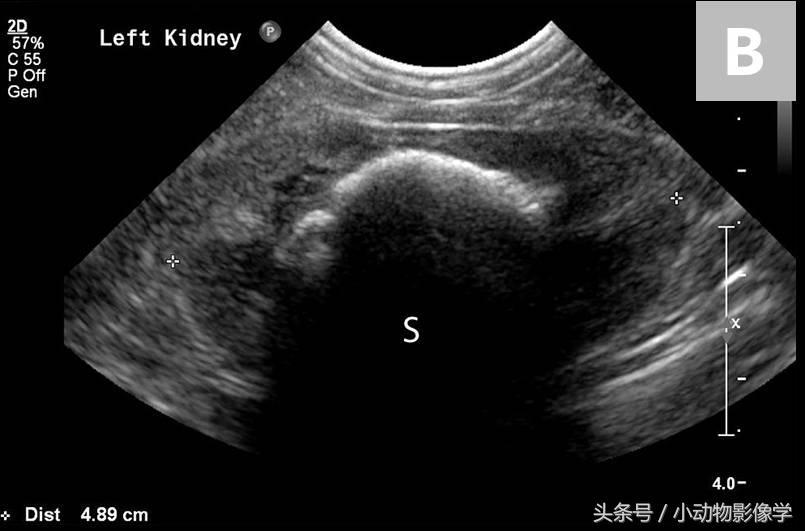

图3B、图3A中左肾的超声图像。可见结石的高回声平滑表面,和由矿化结石引起的明显的远端声影伪像(S)。